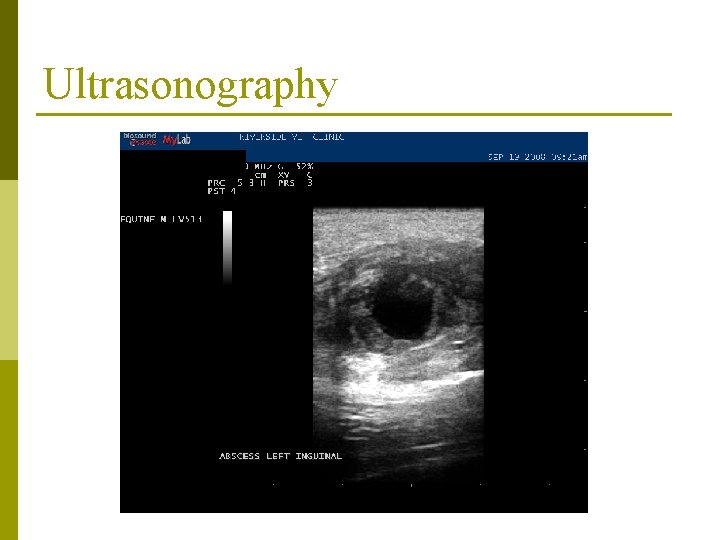

Diagnosis p Index of suspicion p Culture n Gold standard p Ultrasonography p Serology n Internal abscesses

Ultrasonography

Treatment p Time n n “You want me to. . . wait? !” Yeah… p p lets allow the abscess to “cook” for a bit Drainage n Ultrasound guidance p Determine vascularity, depth, site